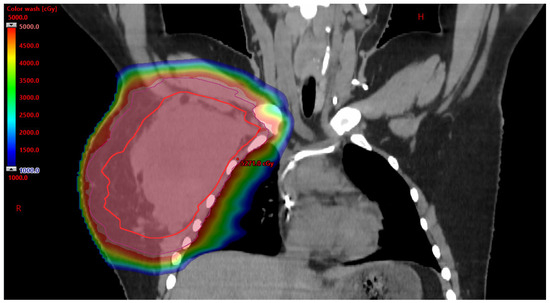

3.2.1. Benefits to PBT